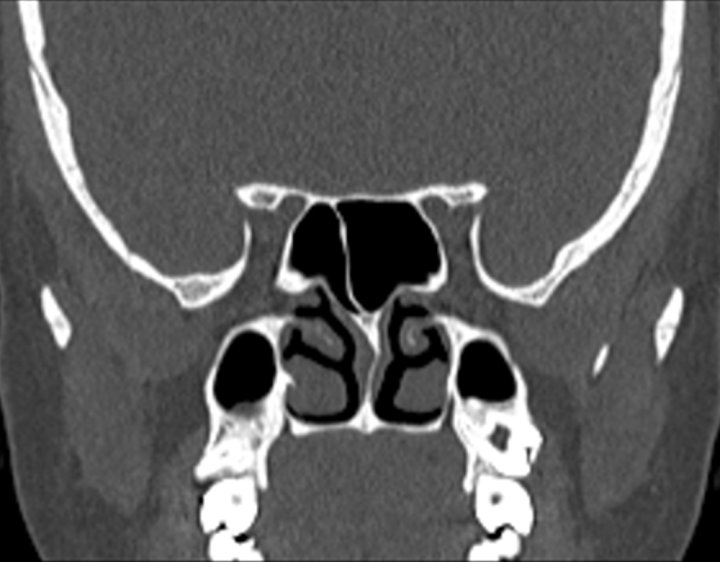

004